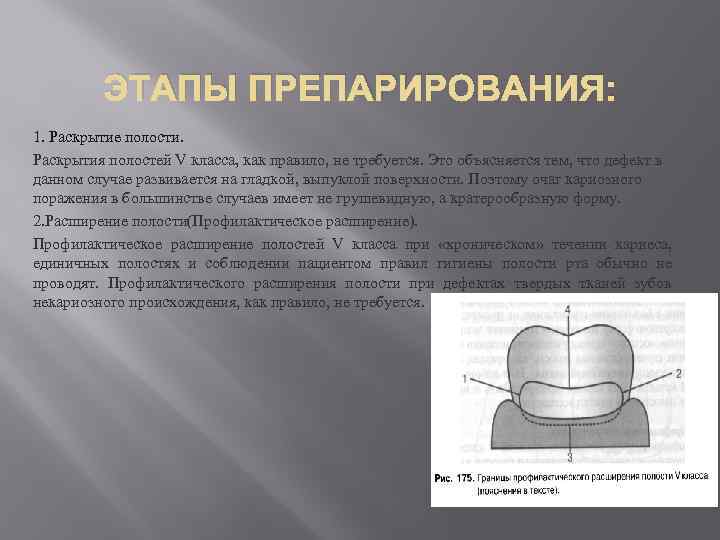

Препарирование кариозных полостей III класса: пошаговое руководство с фото